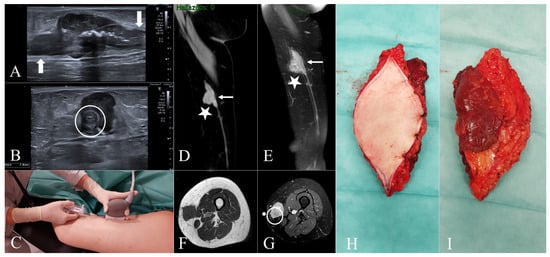

Malignant Tumours Presenting as Chronic Leg or Foot Ulcers

22 May 2021

Our purpose was to collect data on the incidence of malignant skin tumours presenting as chronic leg or foot ulcers in a tertiary centre, and to analyse the frequency and type of initial clinical misdiagnoses in these cases. A retrospective chart rev...